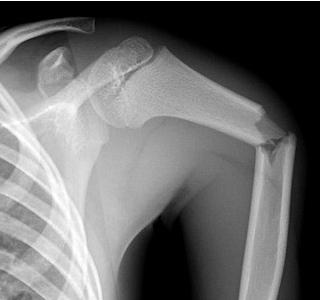

ПІСЛЯ АВТОМОБІЛЬНОЇ АВАРІЇ НА РЕНТГЕНОГРАМІ ВИЯВЛЕНО ПЕРЕЛОМ КІСТКИ В ДІЛЯНЦІ ХІРУРГІЧНОЇ ШИЙКИ. ЯКА КІСТКА МАЄ ТАКУ ШИЙКУ?

варіанти відповідей

ПЕРЕЛОМ ЯКОЇ КІСТКИ І В ЯКІЙ ЇЇ ЧАСТИНІ ВИ БАЧИТЕ?

ГОЛОВКИ HUMERUS

ДИСТАЛЬНОГО ЕПІФІЗА HUMERUS

ШИЙКИ FEMUR

ГОЛОВКИ FEMUR

ГОЛОВКИ RADIUS

ПРОКСИМАЛЬНОГО ЕПІФІЗА HUMERUS

ХІРУРГІЧНОЇ ШИЙКИ HUMERUS

АНАТОМІЧНОЇ ШИЙКИ HUMERUS